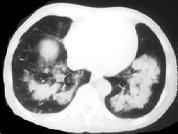

问题 女,34岁,新月体肾炎患者,最近咳嗽咯血,第一次行胸片检查考虑为双下肺感染,抗感染治疗后无明显好转,症状加重,4天后复查并行CT检查如图,应考虑为 ( )

选项 A.肺泡蛋白沉着症 B.肺含铁血黄素沉着症 C.双下肺肺炎 D.肺出血肾炎综合征 E.韦格肉芽肿

答案 D